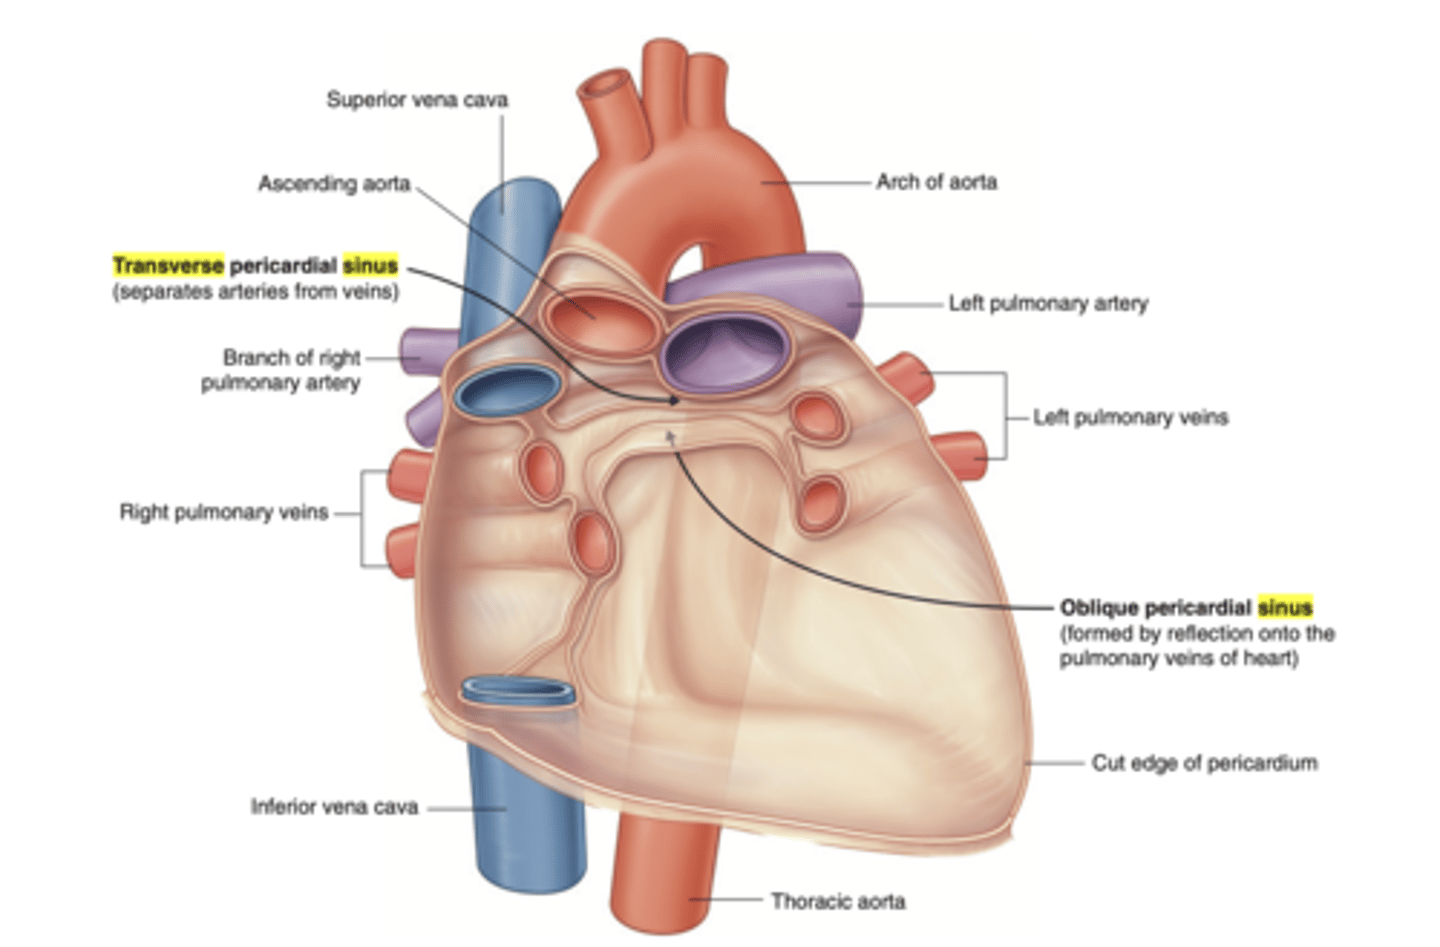

What are the pericardial sinuses and their relevance?

. transverse sinus

. oblique sinus

. Allow for the passage of structures such as blood vessels

. Clinically significant as potential sites of fluid accumulation.

What is the transverse sinus of the pericardium ?

. space posterior to the aorta and pulmonary trunk

. anterior to vena cava

EMBRIOLOGICALLY COMES FROM THE DISINTEGRATION OF THE DORSAL MESOCARDIUM

Clinical significance of the transverse sinus?

Surgeons use it during cardiac procedures.

By passing a finger or clamp through the sinus they can isolate these arteries and control blood flow to the heart during surgeries like coronary artery bypass grafting (CABG).

What is the oblique sinus of the pericardium?

Area where the parietal pericardium reflects (transition) into the visceral pericardium.

Posterior to the heart, cradled by the left atrium and the pulmonary veins.